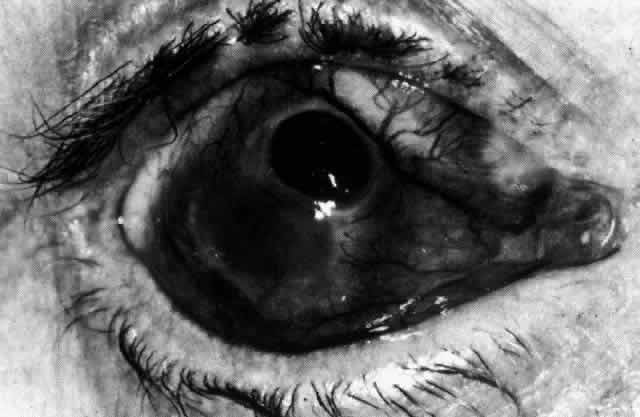

Fig. 44. Necrotizing scleritis. An avascular patch is seen in red-free light. If left untreated, this will progress to the situation found in Figure 45.

Fig. 45. Necrotizing scleritis. An area of necrosis is evident in the eye of this patient with localized Wegener's granulomatosis. The conjunctiva adjacent to the white necrotic tissue becomes adherent to the underlying episclera.